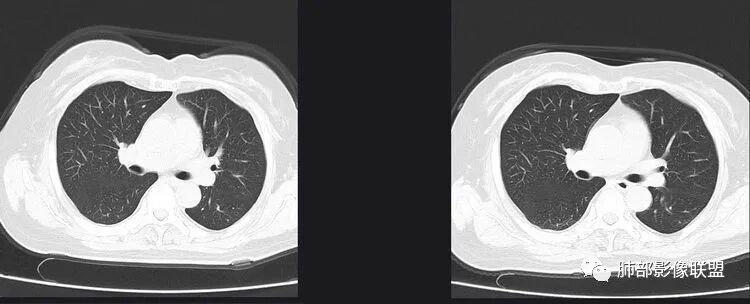

以下是两个时间点左右对比

2019.11.26  👇                           2020.01.20👇                                            2019.11.26片

2020.01.20片